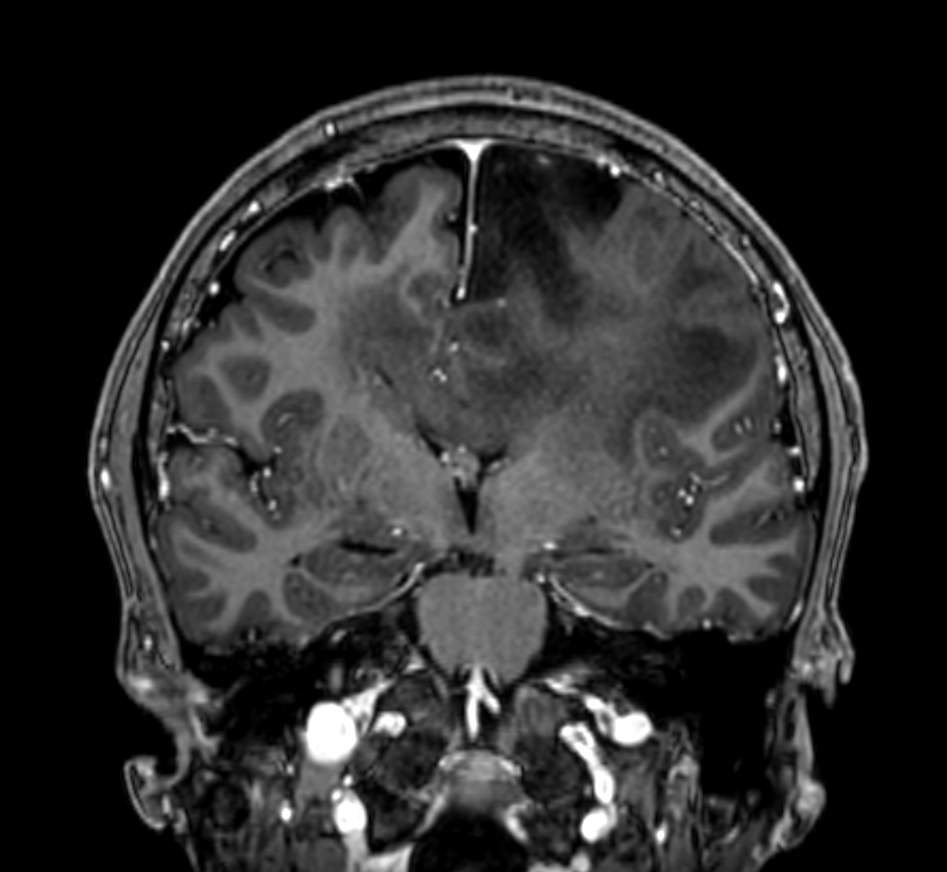

3D T1w TFE - Post-gado (coronal reformat)